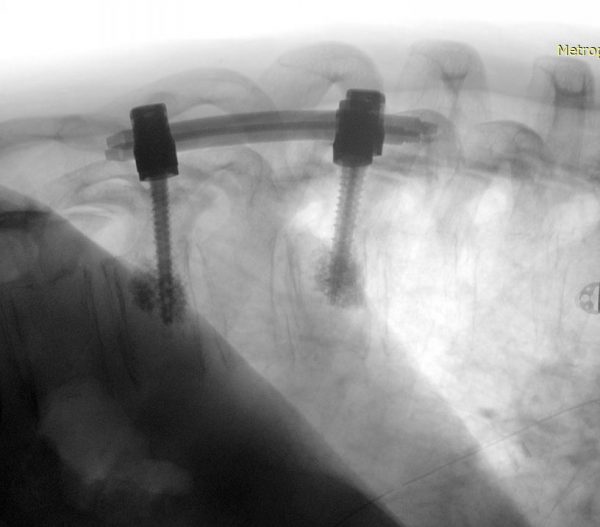

Παράδειγμα εξωσκληρίδιου όγκου: Ασθενής Άρρεν, 73 ετών, με γνωστή μεταστατική μάζα στον Θ10 σπόνδυλο, η οποίοα προκαλεί σημαντική στένωση του σπονδυλικού σωλήνα και πίεση επί του νωτιαίου μυελού. Διενεργήθη αποσυμπίεση του νωτιαίου μυελού και διαδερμική σπονδυλοδεσία/σπονδυλοπλαστική Θ9-Θ10. Μετεγχειρητικά ο ασθενής ανέφερε σημαντική πίεση του άλγους του και σημαντική βελτίωση της βάδισης.

(Προσωπικό Αρχείο Νευροχειρουργού Π. Σταυρινού)

Χειρουργική Αντιμετώπιση: Οι ενδείξεις και ο τρόπος χειρουργικής αντιμετώπισης εξαρτώνται απολύτως από τον τύπο του όγκου. Πρωτοπαθείς (μη-μεταστατικοί) όγκοι των σπονδύλων χρειάζονται ριζική αφαίρεση με σπονδυλεκτομές. Σε περίπτωση μεταστάσεων συνήθως αρκεί η αποσυμπίεση των νευρικών δομών και η συμπληρωματική ακτινοβολία. Το αν υπάρχει ένδειξη για χειρουργείο σε ασθενή με μεταστατική νόσο σπονδυλικής στήλης είναι κάτι που πρέπει να συζητηθεί και να συναποφασιστεί με τους ογκολόγους. Για ενδοσκληρίδους όγκους όπως πχ. μηνιγγιώματα ή νευρινώματα, καθώς επίσης για ενδομυελικούς όγκους (πχ. αστροκυττώματα ή επενδυμώματα) η θεραπεία είναι η ολική χειρουργική αφαίρεση. Συνήθως χρησιμοποιούνται ελάχιστα επεμβατικές μέθοδοι ενώ αποφεύγεται η καταστροφή των υγιών ιστών και δομών της σπονδυλικής στήλης (Εικόνα 3). Μερικοί όγκοι, όπως πχ. το λίπωμα νωτιαίου μυελού, αφαιρούνται ιδιαίτερα αποτελεσματικά με τη χρήση λέιζερ (laser) (Εικόνα 4).